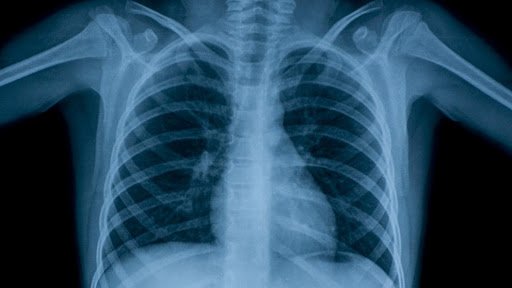

De enero a la fecha la coordinación de Tuberculosis en la Jurisdicción Sanitaria V registra un total de 191 casos de tuberculosis, la mayor cifra corresponde a casos detectados por la Secretaría de Salud, le sigue el IMSS y después ISSSTE con 6; comportamiento que al año casi es similar al que se presentó en el 2020.

La mayoría de los casos son pacientes en edad productiva de 25 a 45 años, pero en el 2021 se han atendido pacientes de 14, 15 y 16 años; en un porcentaje más alto son hombres a los que se les ha detectado tb.

Señaló que en cuanto a cifras van más o menos a la par con el año pasado, no se ha disparado como se esperaba, pero si se ha tenido casos de gente joven, jovencitos desde los 14, 15 o 16 años que no se veía tan frecuente; aunque la mayoría está entre los 25 a 45 años que es la edad productiva y generalmente hay más casos de hombres que de mujeres.